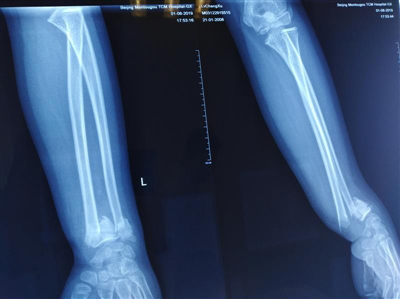

骨折愈合侧位

整复后X线片提示接近解剖复位,40天达到临床愈合,最后随访时患肢外形及功能均完全正常。

2019年8月4日、8日、12日、15日复查X线片见骨折断端位置稳定,与整复当天相比较,未见明显变化。

8月20日复查时X线片见骨折远端轻度向背侧移位,接诊医师在骨折远端背侧放置4层纱布制成压垫以纠正残余畸形。为了避免左前臂肌肉萎缩及腕关节僵硬骨折,从骨折3周后,医生在调整夹板时开始予以理筋松解手法治疗。

9月11日复查查体时见患处无压痛及叩击痛,X线片见骨折线模糊,有足量骨痂形成,符合临床愈合标准,予拆除小夹板,患者左前臂无明显肌肉萎缩,左腕关节无僵硬,未出现筋膜室综合征和神经损伤等并发症。